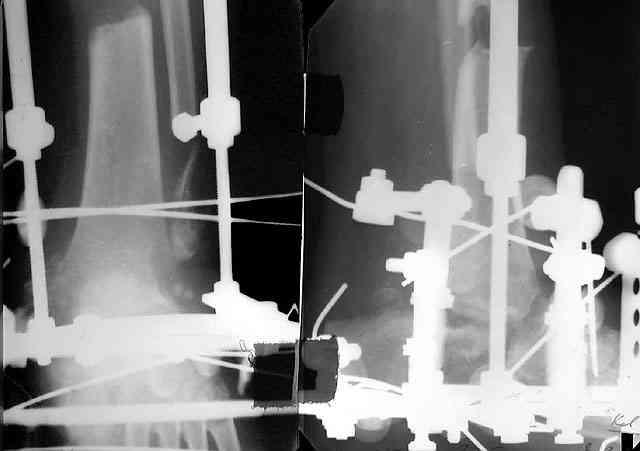

> кости. Выполнена ПХО, фиксация голени и стопы стержневым аппаратом.

> Рана зажила без осложнений. Аппарат демонтирован через 1,5 месяца.

Не адресована другая проблемы - берцово-пяточный блок достигается ценой укорочения конечности на 3-4 см. Поэтому надо предусмотреть что-то для удлинения. У нас в клинике традиционный подход - билокально удлинять большеберцовую кость. Раньше еще и малоберцовую рубили на двух уровнях. Сейчас (спасибо коллегам из форума) пользуемся только

той остеотомией, которая делается для отворачивания кожно-костного лоскута с малоберцовой костью. Фиксируем все это аппаратом (пример в приложении) около 4 мес.